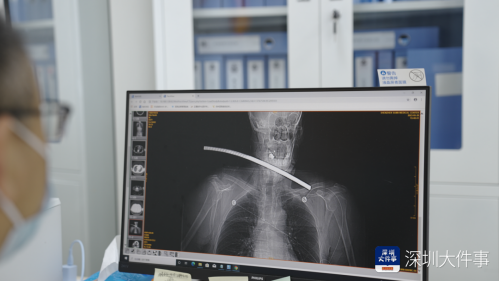

“患者颈内有多处贯穿损伤,颈椎也有受损,我们需要立即送往手术室探查抢救……”急诊科医生对魏伯进行检查后,对魏伯的工友们说道。

钢筋留存在魏伯颈部,魏伯呼吸逐渐困难,手术迫在眉睫。

在术中医生们发现魏伯的状况非同小可,这根钢筋不仅造成了魏伯的颈部贯穿伤,还有大大小小的开放性喉损伤、会厌贯穿伤、颈椎横突骨折并椎静脉破裂。

通过术前仔细观察,医生发现钢筋虽没有直接损伤到魏伯的颈总动脉、颈内静脉等重要结构,但完全贯穿了魏伯的颈部及喉腔,且钢筋表面非常污秽、锈迹斑斑。

钢筋的位置紧贴颈部血管,一不小心就会造成大出血,并且钢筋在患者颈部多停留一秒就多一分危险。